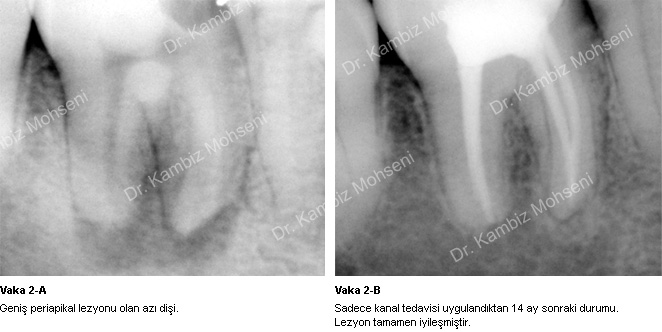

İltihabın sebebi kök kanal sistemindeki mikroorganizmalardır. Uygun bir kanal tedavisi ile ortam mikroorganizmalardan arındırılırsa iltihabın iyileşme şansı oldukça yüksektir. Bu konuyla ilgili örnek vakaları inceleyebilirsiniz;

Vaka 2-A, 2-B, 4-A, 4-B ve 5-A, 5-B.